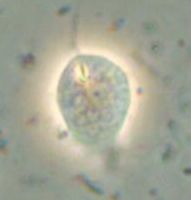

ブラジルリーシュマニア:リーシュマニア・ブラジリエンシス(Leishmania braziliensis)

中南米の森林に生息するげっ歯類、ナマケモノ、サルの皮膚のリーシュマニア症の原因虫ですが、しばしばヒトの鼻咽頭に病変を生ずることがあります。